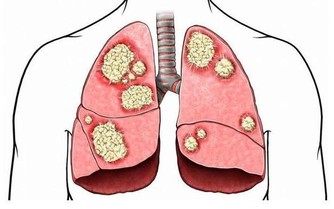

他迅速撥打120, 將蘇煜拉到了當地一家醫院,經檢查醫生拿著拍的片子說,「這治不了,肺都爛了。」蘇先生便帶著兒子趕到了省胸科醫院。 網咖人員聚集、空間密閉,易感染結核病菌 在省胸科醫院內,醫生通過檢查確診,蘇煜患的是嚴重肺結核,大部分肺已經被結核菌侵蝕掉。同時,他還伴有胸腔積水、上消化道出血。 經過一系列治療後,蘇煜逐漸甦醒過來。面對父母,他說得最多是「後悔」。 「前一段時間,剛接診過一個病人,也是20歲左右的小夥子,因為長期泡網吧,結果感染上了結核性腦膜炎,到醫院不到兩天就死了。」省胸科醫院一位醫生說。 「集聚的人群,密閉的空間,很容易感染結核病菌。」這位醫生說,上網容易導致疲勞、自身免疫系統功能下降,再加上網咖的人員流動性大,空氣環境不好,一旦有一個傳染源,網吧裡的其他人很容易感染上。 網吧的空氣質量到底有多差?河南電視台《民生大參考》通過專用的雷射粉塵儀,實地檢測了一下當地市區部分網咖的空氣品質,結果讓人震驚!有網吧的pm2.5濃度最高的達到了2.1毫克每立方米,也就是2100微克每立方米!!

醫生提醒,肺結核病主要是通過病人咳嗽、打噴嚏或大聲說話噴出的飛沫傳播給他人,很多一開始以為是普通感冒、慢性支氣管炎等,但是如果咳嗽、咳痰症狀持續兩週以上,或者痰中帶血,就應該引起注意,盡快到醫院做檢查。 想不到長期待在網咖會有這種性命安全的危險! 請分享給身邊常待網咖的年輕人或成年人,多一個人看到,多一份提醒!!